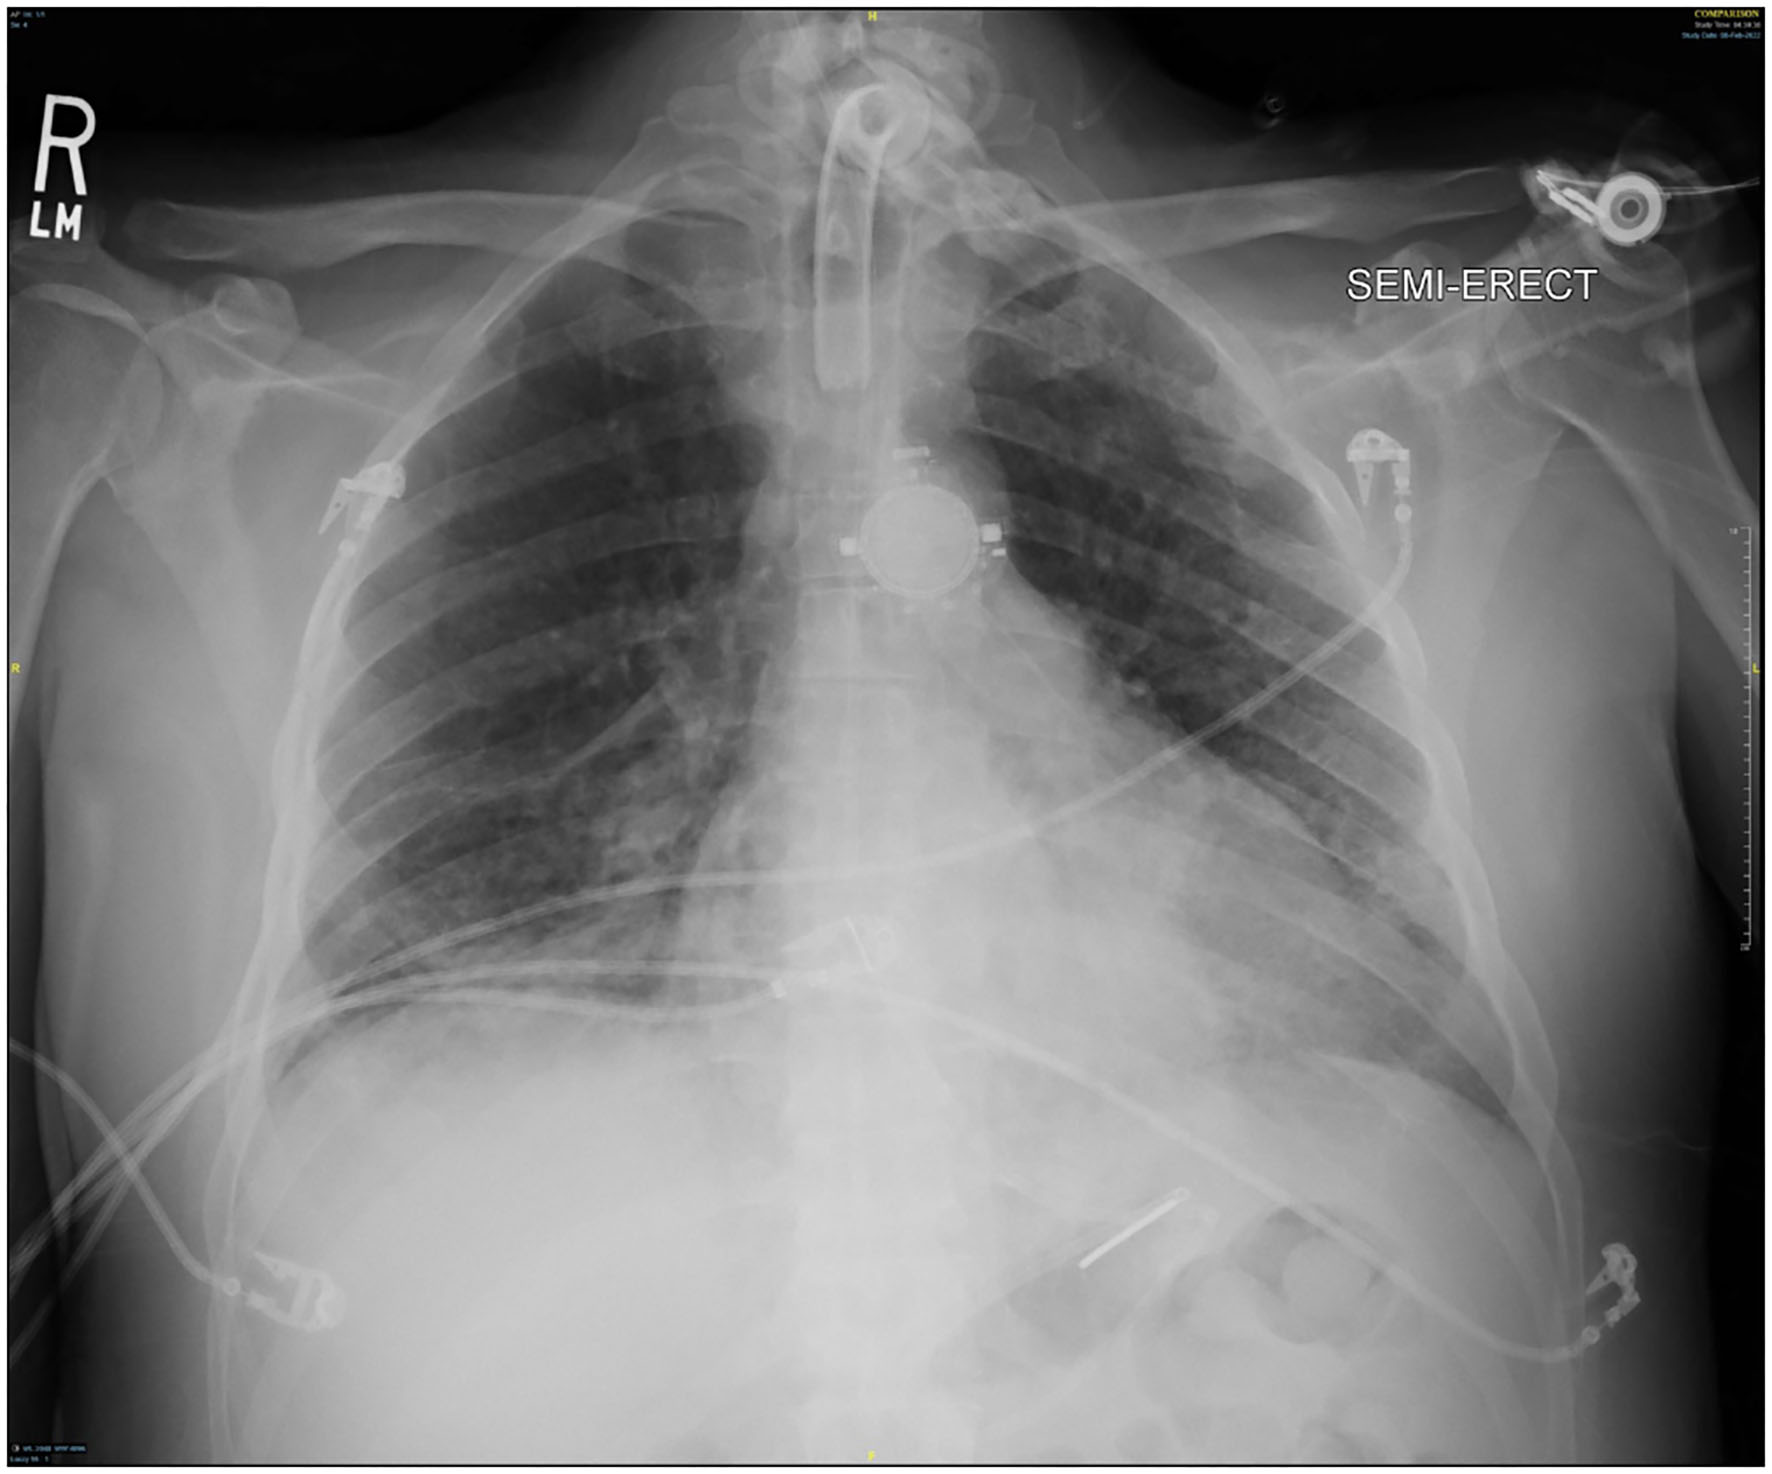

Several days after tracheostomy (hospital day #18, VV ECMO day #11) hemoptysis developed and it persisted despite holding heparin drip and normal platelet counts. His chest x-ray demonstrated bilateral opacifications (Figure 1). Dark blood was suctioned continuously from the tracheostomy and hemoglobin repeatedly dropped requiring transfusions. VV ECMO settings were increased to 100% FiO2 as the VV ECMO sweep was maximized to 11 L/min to maintain SpO2 >85%. Bedside bronchoscopy revealed massive bleeding in the left and right main bronchi. Ice cold saline and epinephrine lavage failed to control the bleeding, thus the site of bleeding was unable to be identified. Despite the evacuation of more than 500 cc of blood under bronchoscopy, there was continued hemorrhage from both main bronchi (Figure 2). The tracheostomy tube was removed to examine the stoma, and no active bleeding was identified in that area. A direct suction was then attempted, inserting a Yankauer suction catheter into the trachea via the tracheostomy stoma (Figure 3). This was also unsuccessful in clearing the airway. In further attempts to control bleeding, continuous bronchoscopy was performed for 4 h with the maintenance of adequate SpO2 >85% despite discontinuation of the ventilator.

Figure 1

Chest x-ray at the time of hemoptysis.